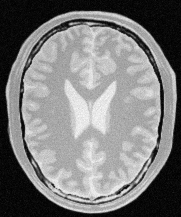

ITK is an open-source, cross-platform system that provides developers with an extensive suite of software tools for image analysis. Among them, Node-ITK is a node.js wrapper which built on top of ITK, intended to facilitate its use in rapid prototyping, education, and web servies for Medical Image Processing.Its Origins by My master thesis--jolly, a new Framework for Medical Image Processing